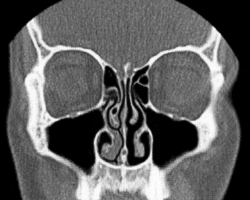

Le cycle nasal est l'alternance inconsciente d'une congestion (ou gonflement) et d'une décongestion (ou dégonflement) partielles des fosses nasales chez l'homme et d'autres animaux[1],[2],[3],[4]. Il en résulte un débit d'air plus important dans une narine avec une alternance périodique entre les narines. Il s'agit d'une congestion physiologique des cornets nasaux due à l'activation sélective d'une moitié du système nerveux autonome par l'hypothalamus. Elle ne doit pas être confondue avec l'obstruction nasale.